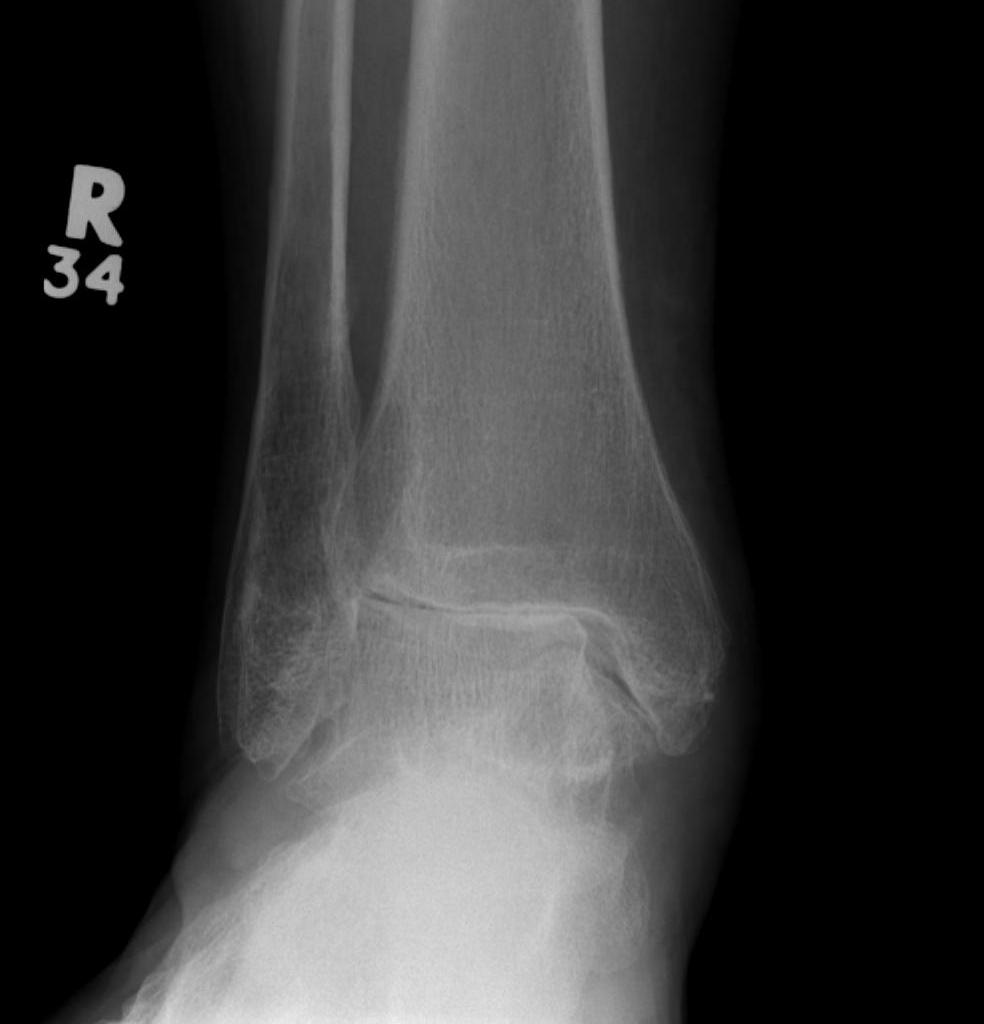

Bimalleolar and Trimalleolar Fractures

| Bimalleolar fractures | Trimalleolar fractures |

Fibular + medial malleolus Fibular + posterior malleolus |

Fibular + Medial malleolus + Posterior malleolus Anterior impingement